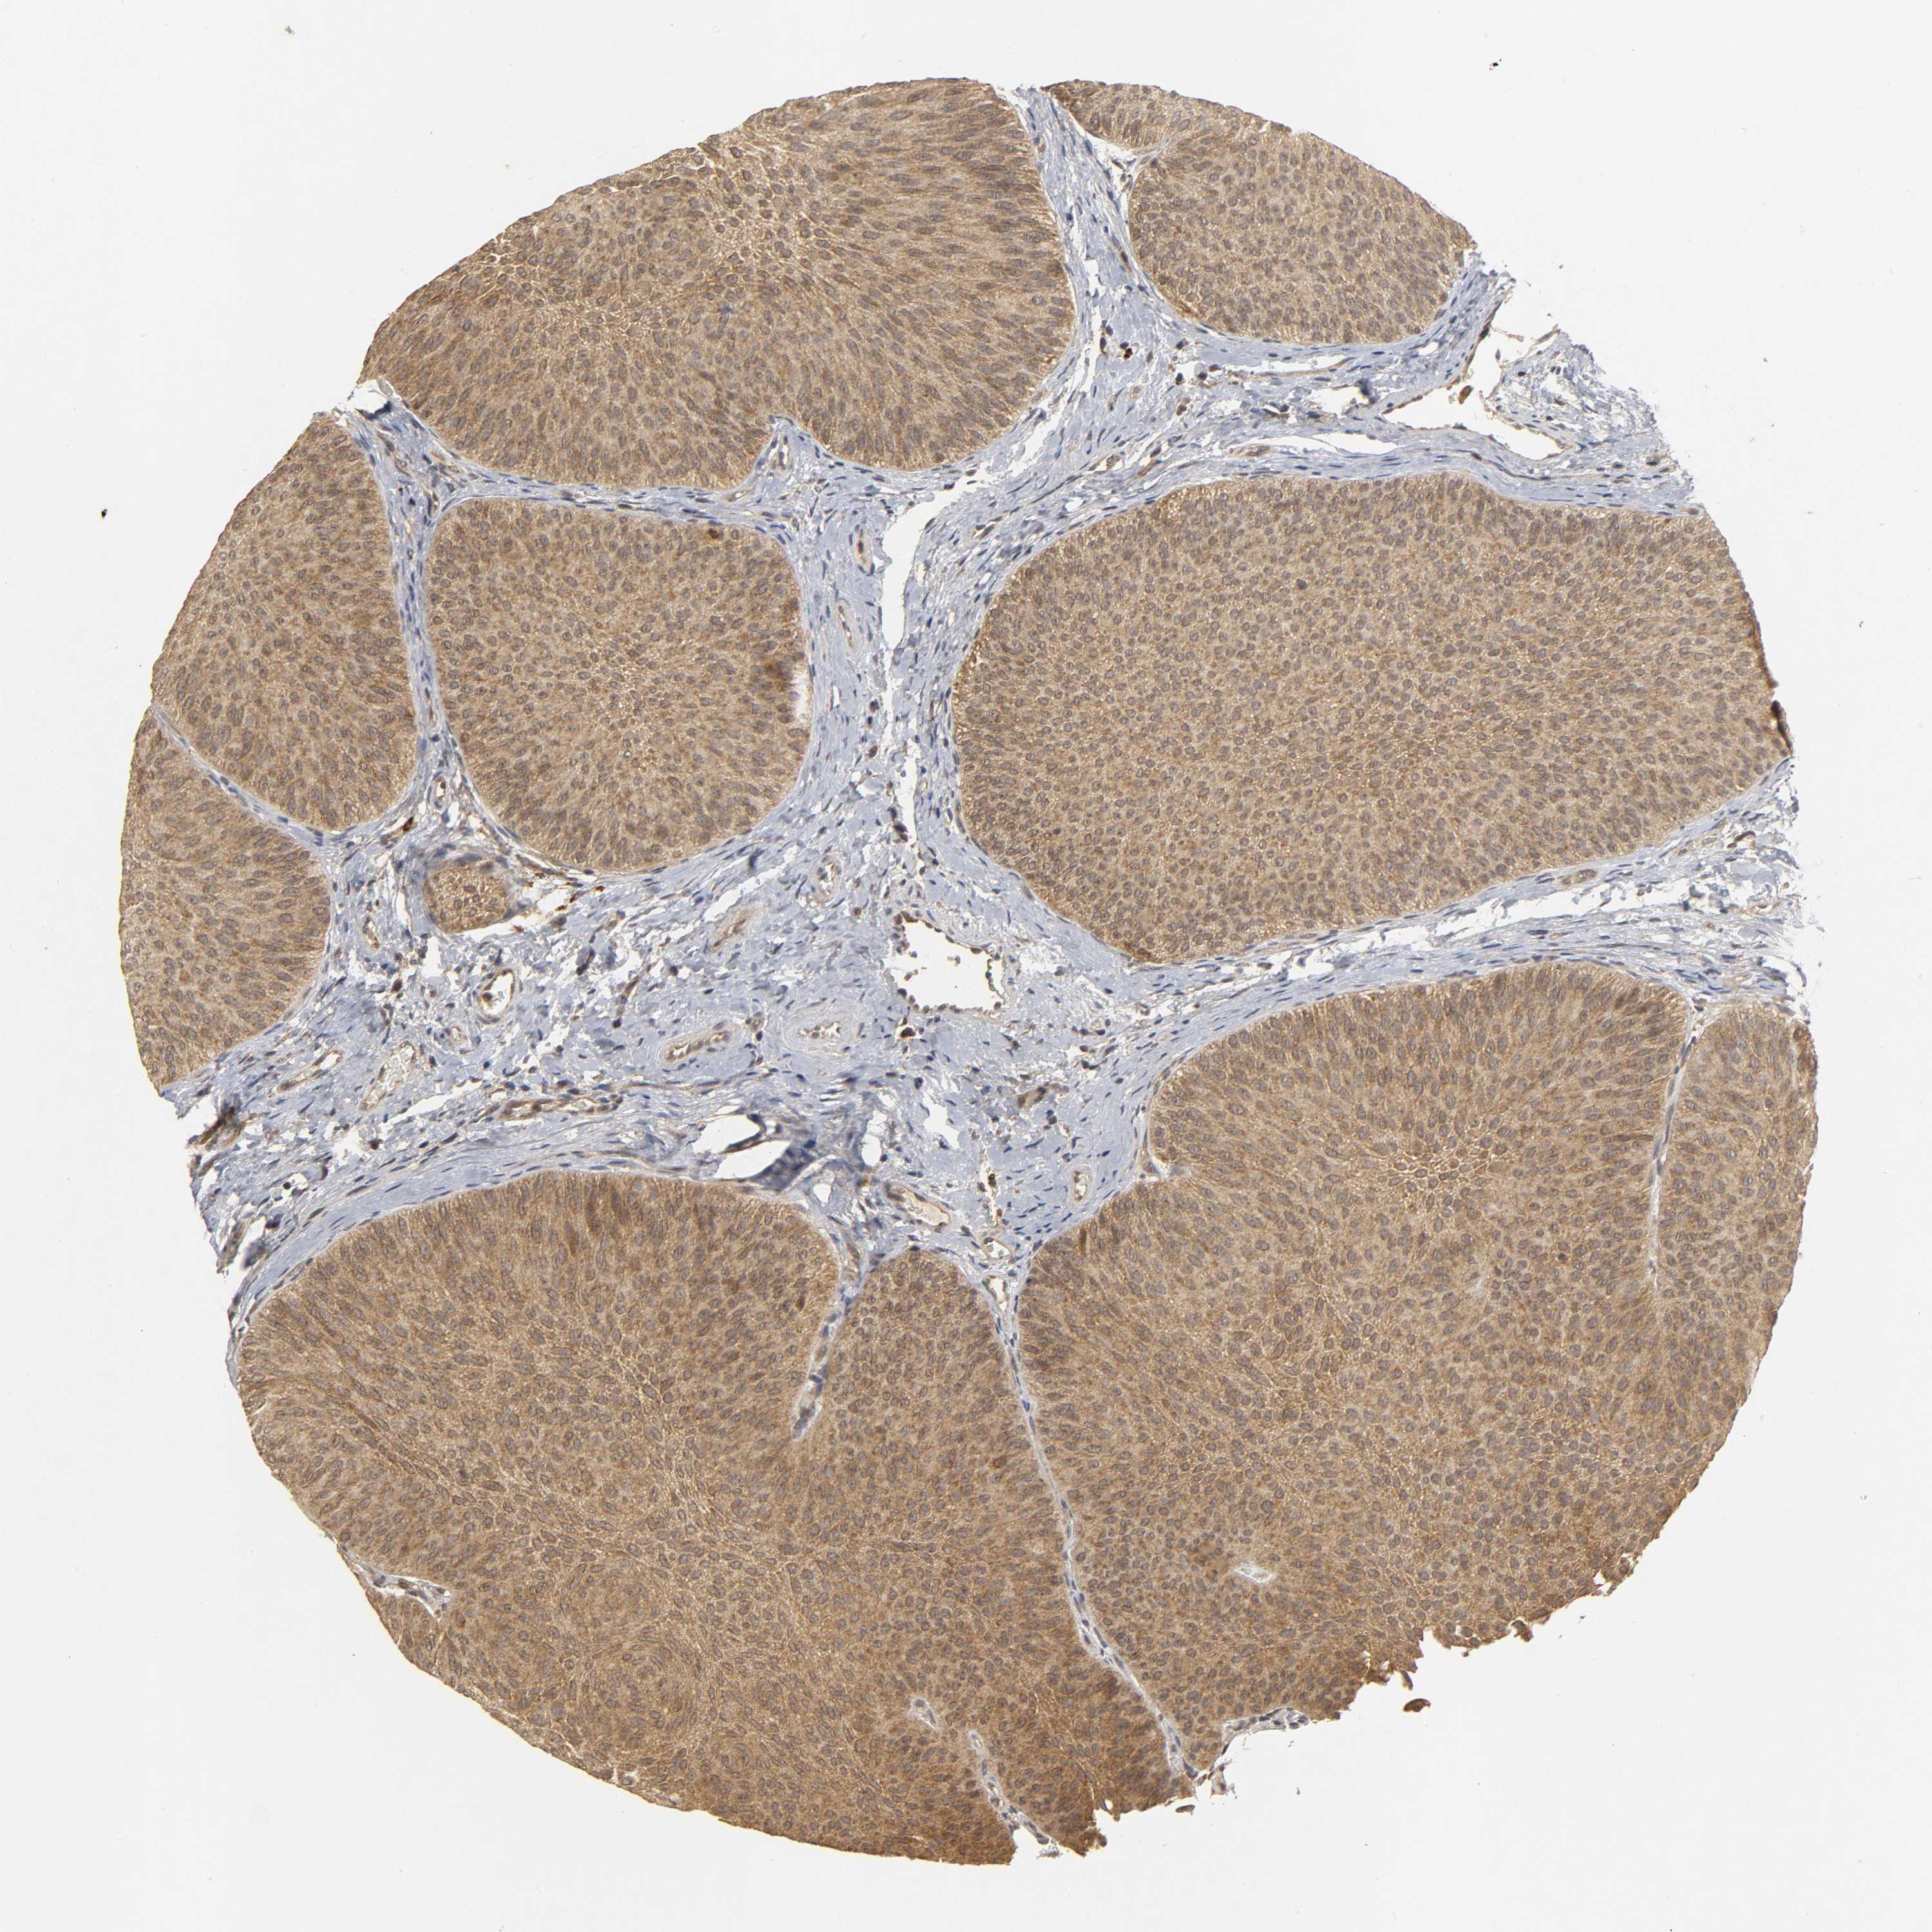

UROTHELIAL CANCER - Protein expressioni

A mouse-over function shows sample information and annotation data. Click on an image to view it in a full screen mode. Samples can be filtered based on level of antibody staining by selecting one or several of the following categories: high, medium, low and not detected. The assay and annotation is described here.

Note that samples used for immunohistochemistry by the Human Protein Atlas do not correspond to samples in the TCGA dataset.

Antibody stainingi

Antibody staining in the annotated cell types in the current human tissue is reported as not detected, low, medium, or high, based on conventional immunohistochemistry profiling in selected tissues. This score is based on the combination of the staining intensity and fraction of stained cells.

Each image is clickable and will lead to virtual microscopy that enables deeper exploration of all samples and also displays staining intensity scores, fraction scores and subcellular localization as well as patient and tissue information for each sample.

Antibody HPA019805

Antibody HPA020599

Antibody CAB004605

Staining

High

Medium

Low

Not detected

Intensity

Strong

Moderate

Weak

Negative

Quantity

>75%

75%-25%

<25%

None

Location

Nuclear

Cytoplasmic/membranous

Cytoplasmic/membranous,nuclear

Urothelial carcinoma, Low grade

Urothelial carcinoma, High grade